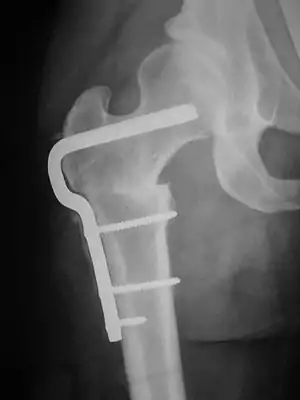

القطع العظمي في الورك

هناك نوعان رئيسان من القطوع العظمية يُستخدمان لتقويم خلل التنسج الوركي وتشوهات الورك، وذلك من أجل تحسين الارتصاف أو تحسين التفاعل بين الحُقّ (التجويف) مع رأس عظمة الفخذ (الكرة). هذان النوعان هما قطع العظم اللامسمى (بالإنجليزية: innominate osteotomies) وقطع عظم الفخذ (بالإنجليزية: femoral osteotomies)، وفيهما يُقطع العظم ويُعاد تشكيله أو قد يُزال جزئياً، من أجل تصحيح ارتصاف وتلاقي أسطح المفصل لحمل وزن الجسم بطريقة صحيحة.

يتم تعديل الجزء المطلوب من عظم الورك عن طريق الجراحة، وقد تم تطوير العديد من الطرق الجراحية المختلفة لتحقيق ذلك، وتعريف كل طريقة بحسب نوع قص العظم ونوع التعديل المطلوب. سُمّيت بعض الإجراءات الخاصة بجراحة الحُقّ على أسماء الجراحين الذين وصفوا لها طرقاً لأول مرة، مثل طريقة سالتر، ديجا، ساذرلاند، شياري ، ومن الأسماء الأخرى واحدة: لودلوف،. بيمبرتون، وجيمس ستيلي. تتم تسمية بعض الطرق على حسب شكل القطع (مثل طريقة: شيفرون Chevron على شكل V ، أو الوتد Wedge)، أو على الطريقة التي يتم بها محاذاة العظام ورصفه (مثل طريقة: دايل Dial = القرص الدوار للهاتف القديم).

قطوع عظم الفخذ (بالإنجليزية: Femoral Osteotomies)، كما يشير الاسم، تنطوي على تعديلات على رأس عظم الفخذ و/أو عظم الفخذ.

بعد اجراء الجراحة مباشرة.